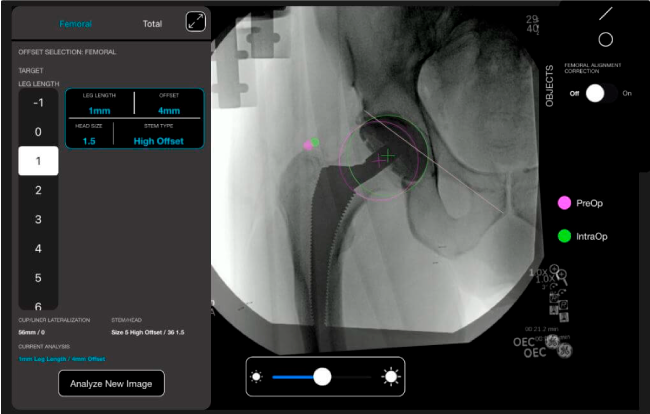

Planeación preoperatoria mediante la creación de plantillas digitales para reemplazo de cadera y análisis intraoperatorio

Mayor nivel de información intraoperatoria facilita la colocación correcta de los implantes:

Desplazamiento y offset para posicionamiento óptimo del componente (vástago) femoral.

Anotaciones digitales y herramientas de análisis de longitud de pierna.

Con tecnología ONETRIAL® que calcula automáticamente el cambio en la longitud de la pierna y el desplazamiento para todas las combinaciones de implantes en una tabla fácil de leer.